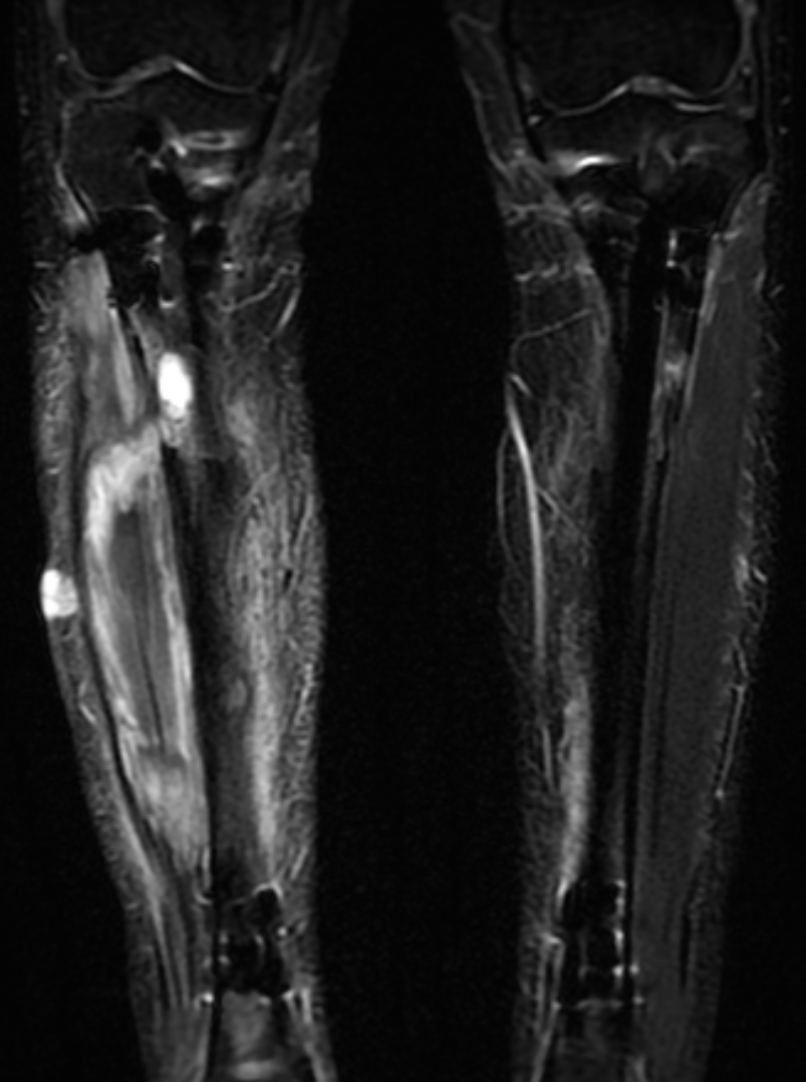

こび@骨延長

@height_llt

僕もほとんど肉が溶けていました。。

術前のMRI 白い部分は肉が液状化してしまった箇所